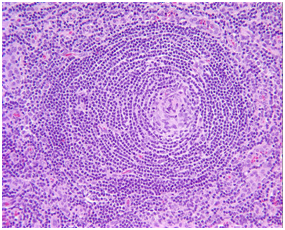

Laboratory Investigations (Table 1) revealed moderate normocytic normochromic anaemia with normal reticulocytic count: hypoalbuminemia with normal 24-hours protein collection in urine: raised acute phase reactants (Erythrocyte sedimentation rate "ESR" and C-reactive protein "CRP"): normal anti- nuclear antibody: anti double stranded DNA: rheumatoid factor and negative tuberculin test. Human immunodeficiency virus (HIV) serology was negative at presentation. Chest X-rayshowed moderate right sided pleural effusion. Computerized tomography (CT) neck: chest and abdomen showed multiple enlarged cervical lymph nodes 1.5*1cm: enlarged bilateral axillary lymph nodes the largest one 2*3cm: multiple enlarged anterior meditational lymph nodes 2.5*2.5cm: moderate right sided pleural effusion: left lower lung lobe pneumonic consolidation: mild hepatomegaly and moderate free ascitis (Figure 1). Exicisional biopsy of an axillary lymph node (Figure 2) was performed and histopathological examination revealed hyaline vascular Castleman's disease ( increased number of follicles with atrophic germinal centers and the inter follicular area showing proliferation of hyalinized capillaries and thick wall blood vessels).Child received adequate supportive care and CHOP regimen as a combination chemotherapy {cyclophosphamide 1000mg/m2 (d1): vincristine 1.5mg/m2 (d1): doxorubicin 40mg/m2 (d1): prednisolone 40mg\m2 (d1-d5)}. After 3 cycles of CHOP: there is marked clinical improvement with disappearance of constitutional manifestations: lower limb oedema: ascitis: pleural effusion and puffiness of the eyes.

Figure 2 Histopathological picture of axillary lymph node showing hyaline vascular castleman's disease with increase number of follicles, atrophic germinal centers, the intermolecular area showing proliferation of hyalinized capillaries and thick wall blood vessels.